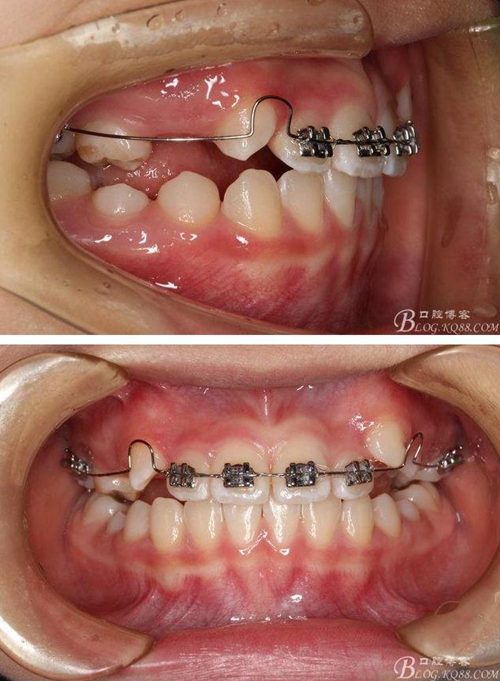

矯治第6個月復(fù)診:前牙反咬合已經(jīng)完全解除,上頜前牙也進(jìn)一步排齊了。后牙咬合接觸改善。